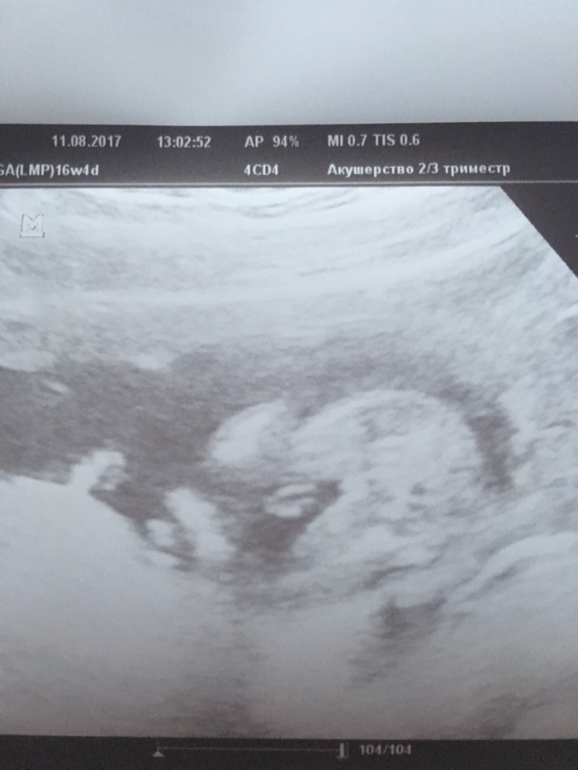

Пол малышаДевчульки, извините за качество фотографий УЗИ, но может все-таки увидите- прав был врач с определением пола, или нет. Кто что думает? Обещали мальчика, срок был 16-17 недель. Врач квалифицированный, аппарат УЗИ современный, клиника наикрутейшая. Сказали, что мальчик 100%. Ничего не отвалится, здесь все очевидно. Можно говорить мужу.

Вот, на нижнем мне больше кажется, что девочка, но эти два кругляшка , непонятные...

Вот по нижнему фото отчётливо видна мошонка.)) мне кажется это мальчик))